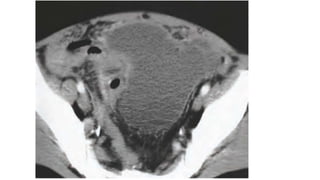

Pelvic Abscess

Clinical presentation

• Back pain, lassitude and fever.

• A swelling may point to the groin as it tracks along iliopsoas.

• Pain may be elicited by passive extension of the hip

• or a fixed flexion of the hip evident on inspection.